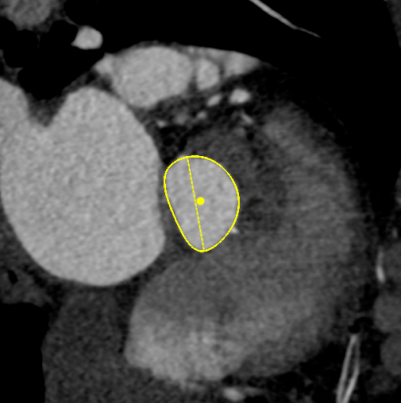

Annulus

长径: 24.8 mm

周长: 68.6 mm

面积: 352.3 mm²

LVOT

长径: 24.3 mm

周长: 66.3 mm

面积: 321.7 mm²

SOV

27.3 x 25.8 x 25.9 mm

STJ

长径: 27.6 mm

周长: 84.4 mm

面积: 566.2 mm²

高度: 13.8mm

RCA

下缘高度 10.2mm

上缘高度 11.9mm

瓣叶长度 12.7mm

LCA

下缘高度 7.1mm

瓣叶长度 11.8mm